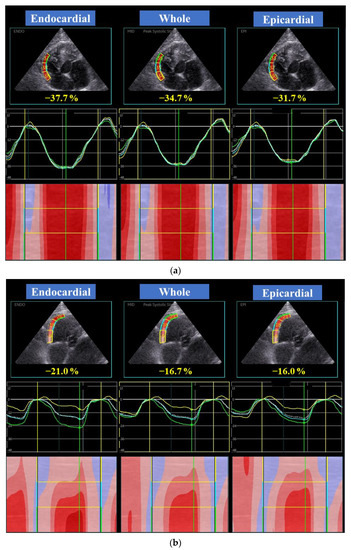

| Global RV longitudinal strain (%) | |||||||

| Whole layer | 22.9 | (16.4, 31.9) | 10 | 31.6 | (27.8, 39.1) | 15 | 0.07 |

| Endocardial layer | 24.9 | (19.0, 34.2) | 10 | 34.8 | (29.6, 42.3) | 15 | 0.10 |

| Epicardial layer | 21.3 | (14.0, 29.8) | 10 | 29.0 | (26.0, 36.4) | 15 | 0.045 |

| Endo/Epi | 1.21 | (1.13, 1.30) | 10 | 1.15 | (1.13, 1.18) | 15 | 0.03 |